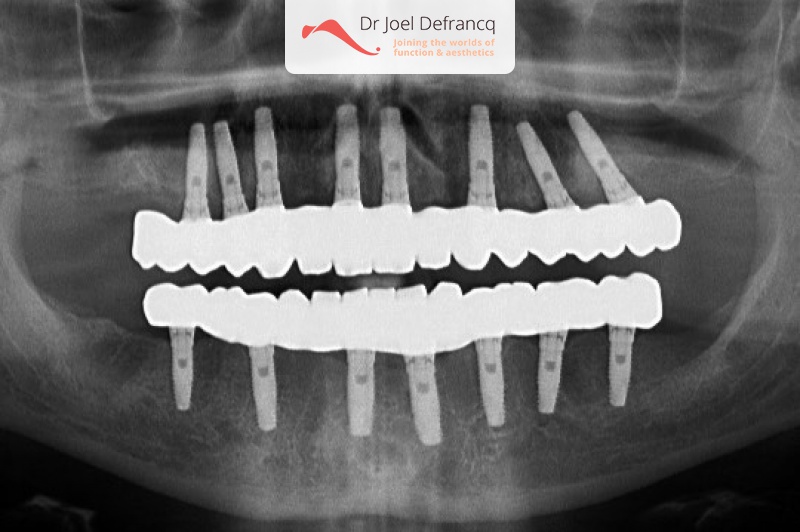

Dagobert: All on four implantaten

Behandeling tandheelkundige implantaten

- Vaste tanden op implantaten (bovenkaak)

- Vaste tanden op implantaten (onderkaak)